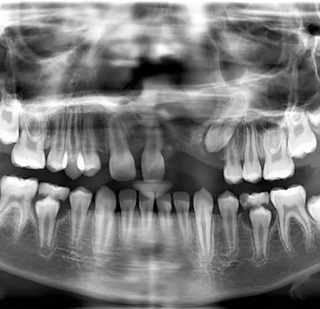

https://radiant3dxray.com/wp-content/uploads/2025/05/OPG1.jpg

OPG

Orthopantomograph (OPG) is a 2-dimensional view of the entire upper & lower jaws from ear to ear. An OPG displays all the teeth of upper & lower jaws on a single film.